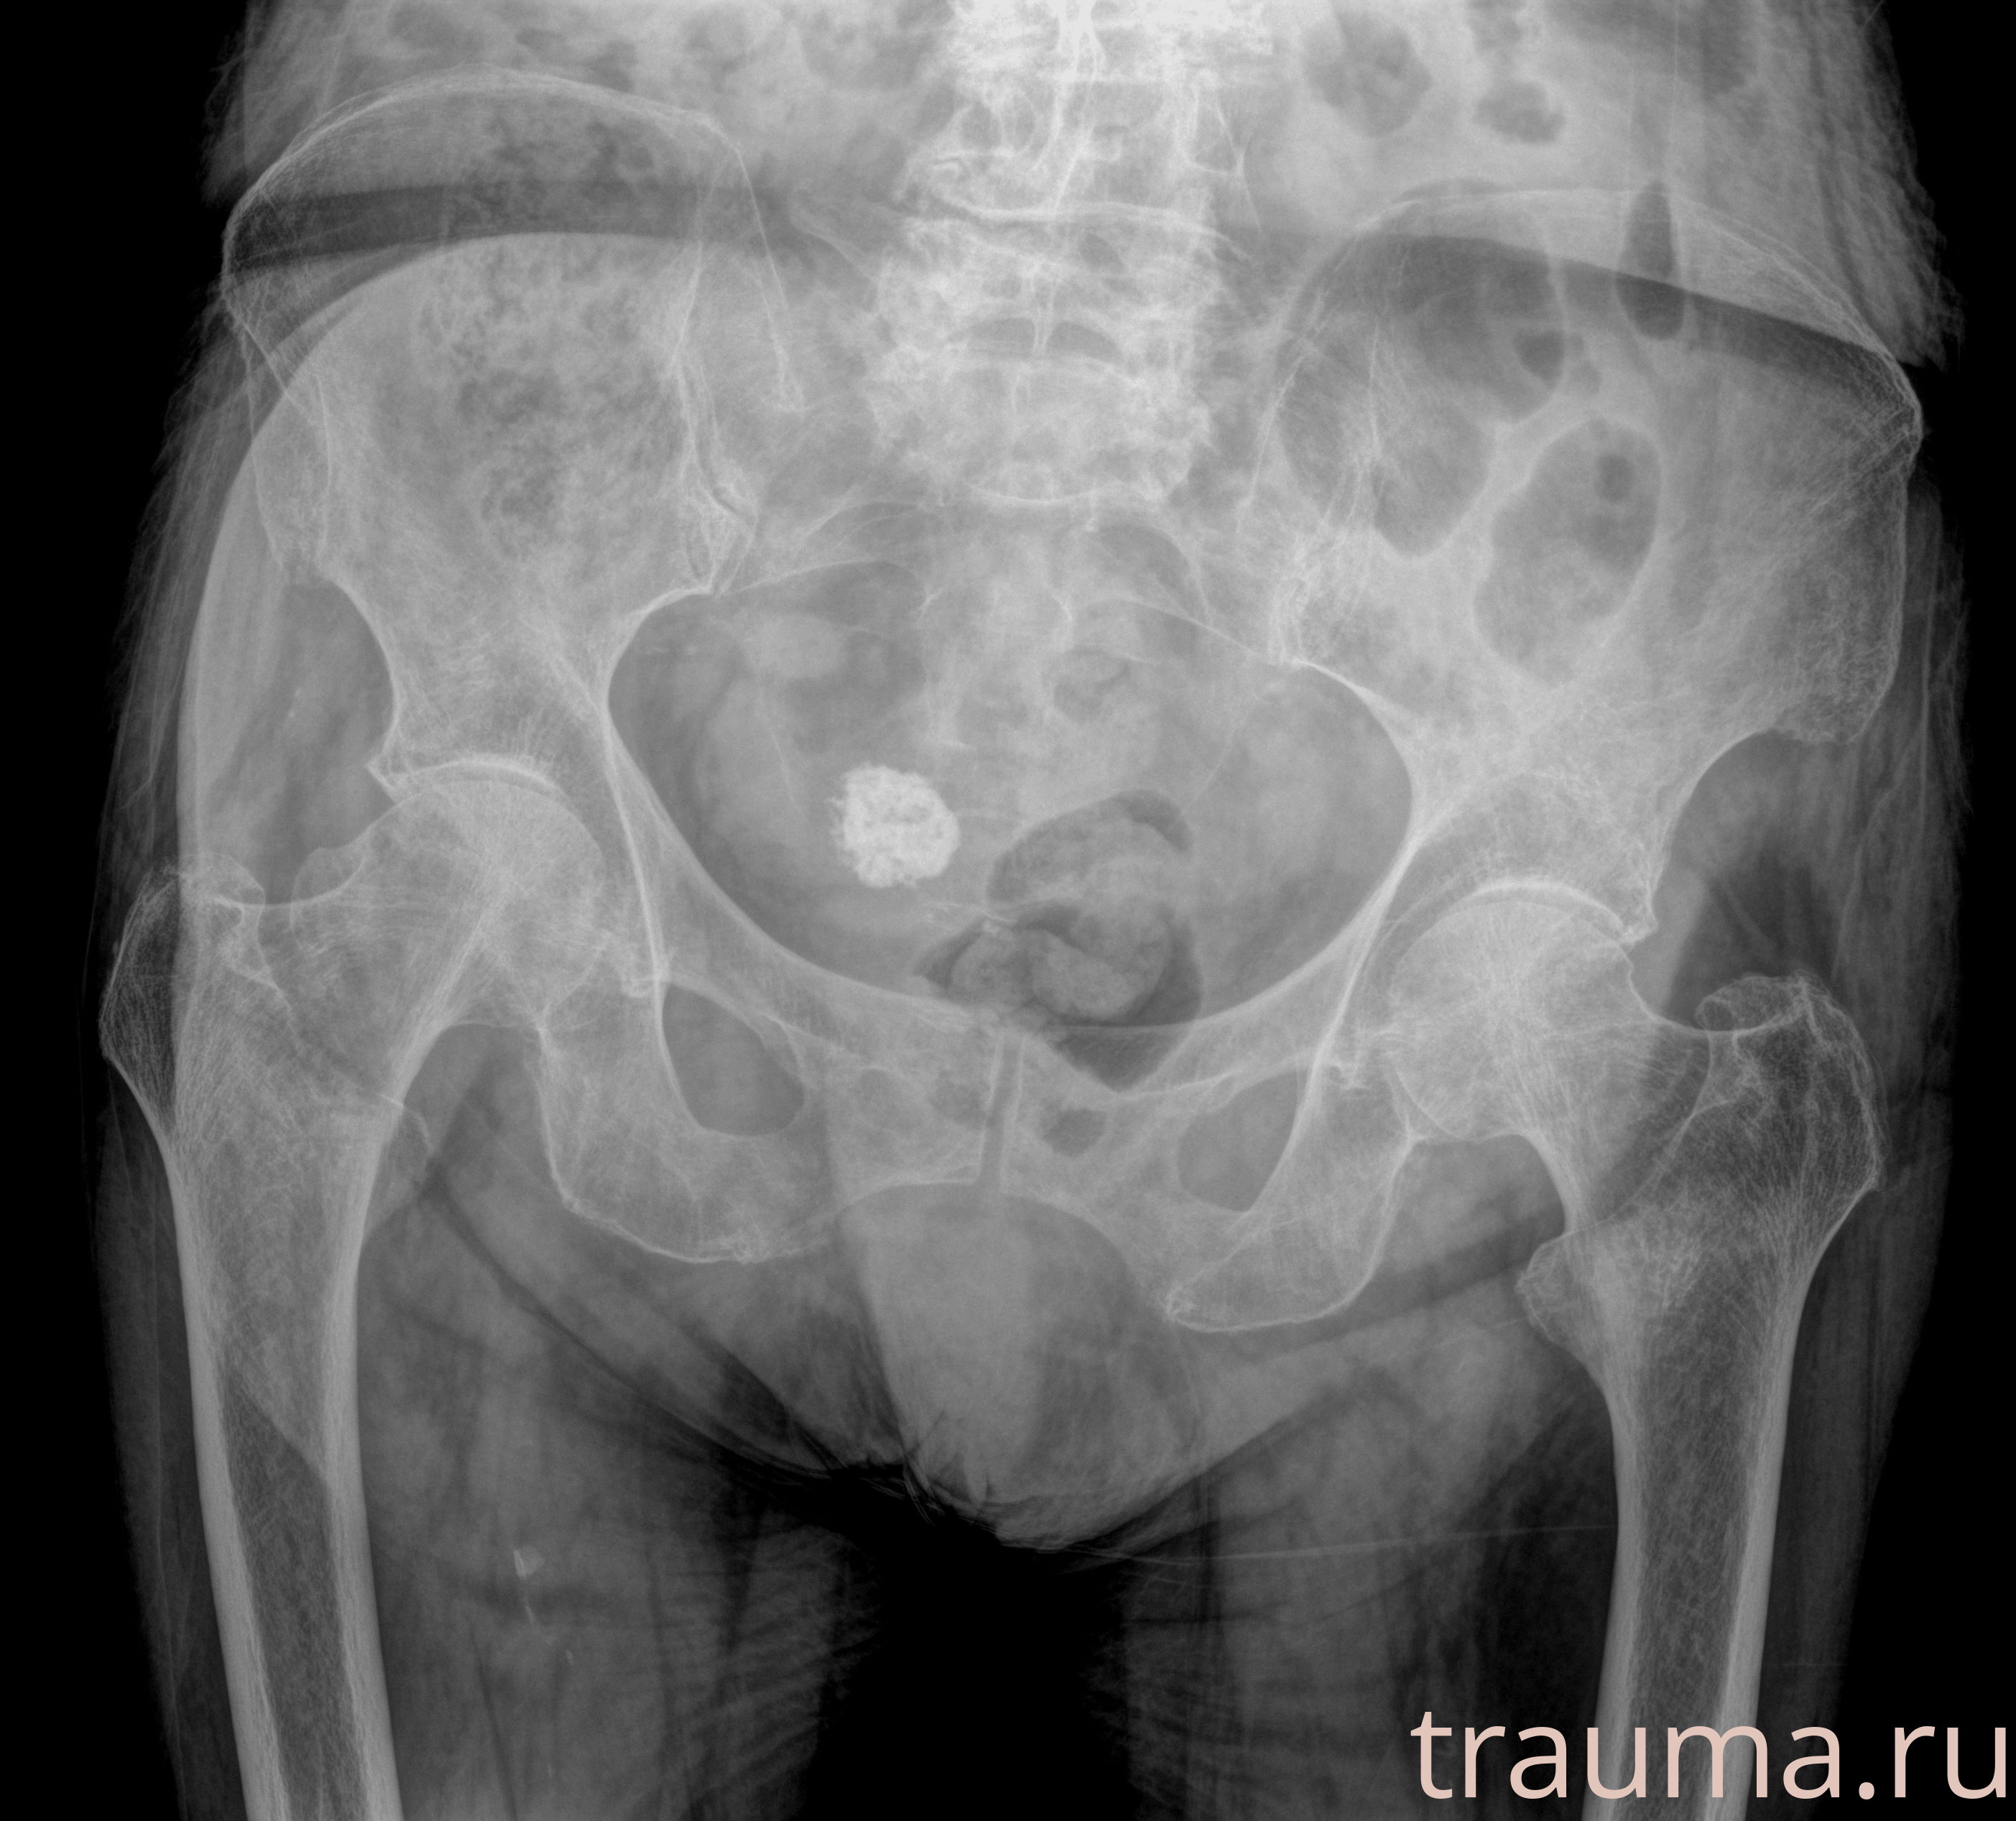

Рентгенограммы

Рентген на дому: по вашему адресу приезжает врач-рентгенолог, травматолог-ортопед с мобильным рентгеновским аппаратом, проводит диагностику травмы или заболевания, делает необходимые рентгенограммы, дает рекомендации по дальнейшему лечению. Получить качественные снимки в домашних условиях возможно благодаря уникальной методике, разработанной МосРентген Центром для института  Склифосовского